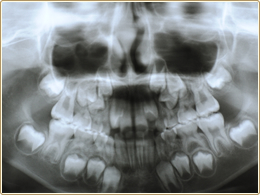

検診時乳歯の数が足りない、癒合歯があると指摘された

乳歯の数が足りない場合や、癒合歯がある場合はその部位の永久歯の数も足りないことがあります。歯の数の確認は、レントゲンを撮れば簡単にできます。先天的に歯の数が不足している場合は、矯正でスペースをつめたり、将来ブリッジやインプラントなどをお勧めする場合もあります。

癒合歯や失活歯の可能性があります。乳歯の癒合歯がある場合はその後に萌えてくる永久歯が先天的に欠如していることが多いので、レントゲン写真で確認する必要があります。

骨の中の永久歯の数や

位置は正常かな?

検査をすることで現在の歯やアゴの状態を確認することができます。レントゲン検査で現在の歯やアゴの状態が確認できますので、将来の予測・現在のどのような治療が必要かアドバイスさせて頂きます。